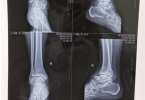

• 轻微脚踝骨折多久能走路

轻微脚踝骨折多久能走路

轻微脚踝骨折一般需要4-8周才能恢复行走功能,具体时间与骨折类型、康复训练及个人体质有关。踝关节由胫骨、腓骨和距骨构成,轻微骨折通常指无移位或稳定性骨折,骨皮质连续性部分中断。临床表现为局部肿胀、压痛和 ...